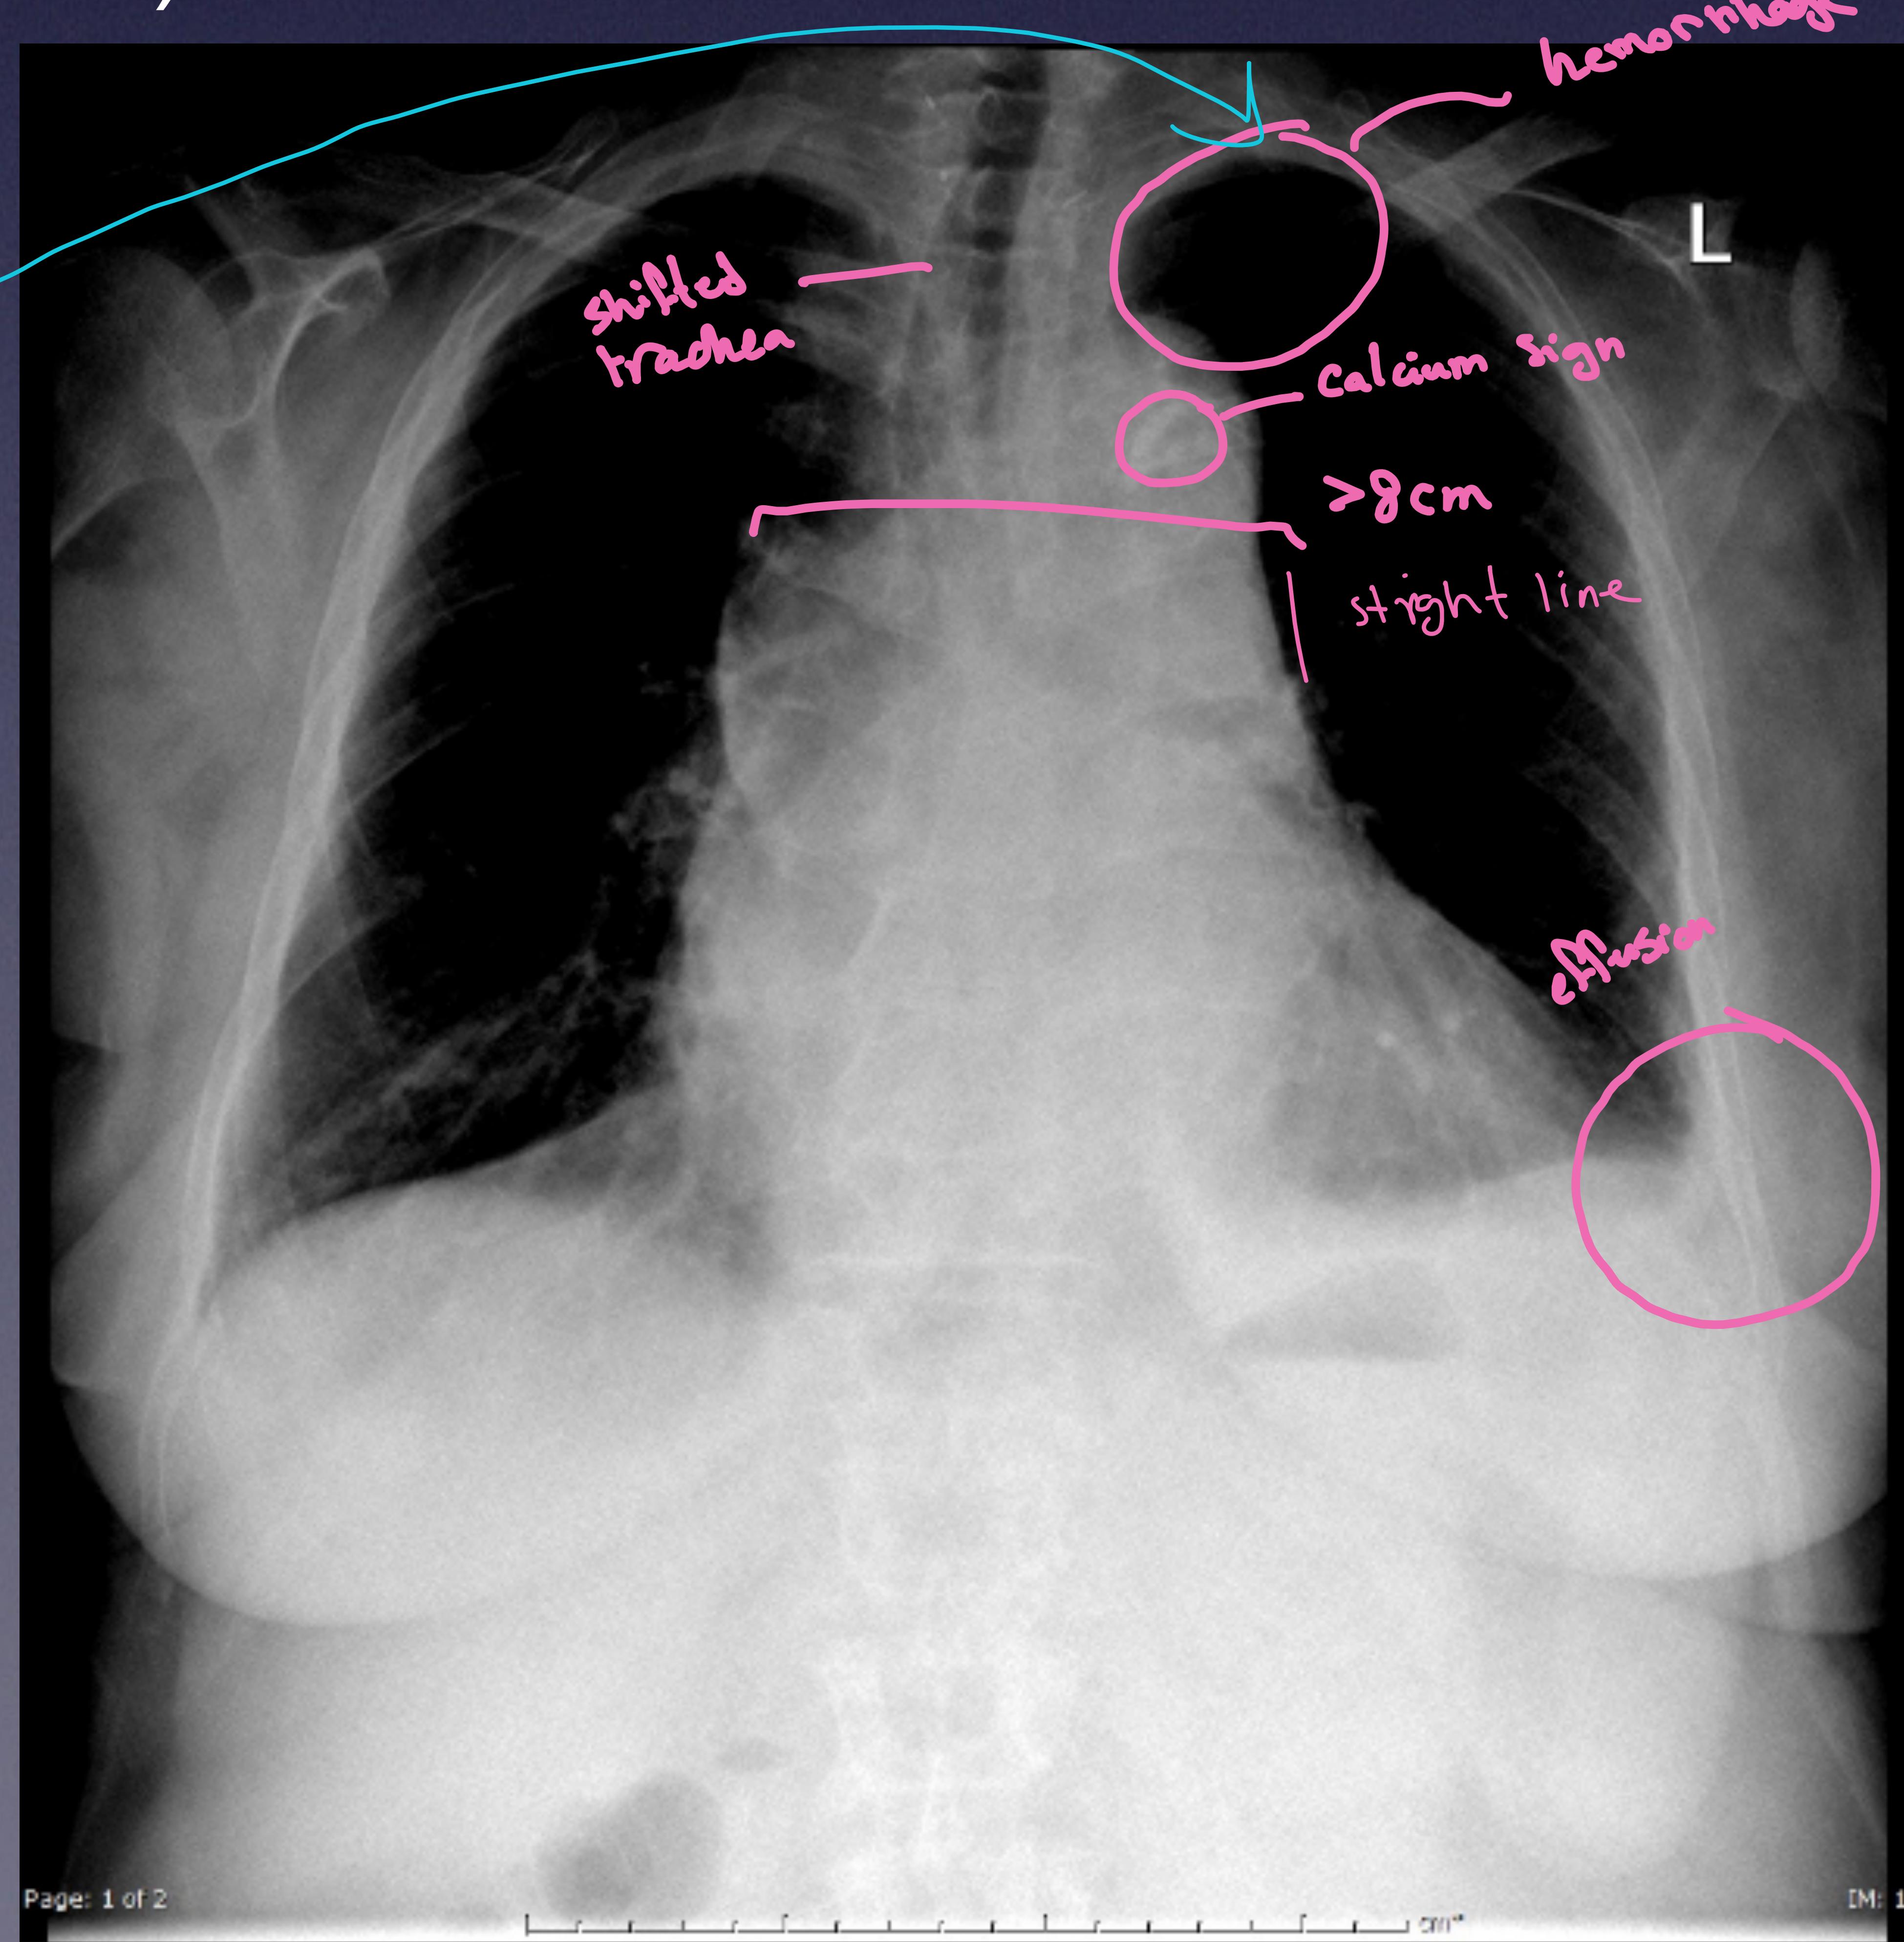

1. Chest X-ray

Note: Normal in 11-16% of cases. Not sensitive.

- Widened mediastinum (> 8 cm) (56-63%)

- Abnormal aortic contour (48%)

- Aortic knuckle double calcium sign (> 5 mm) (14%)

- Pleural effusion (Left > Right, obliterated angle)

- Tracheal shift

- Left apical cap

- Deviated NGT

Chest X-ray showing findings of aortic dissection: shifted trachea, calcium sign, widened mediastinum, hemothorax, effusion, left apical cap.